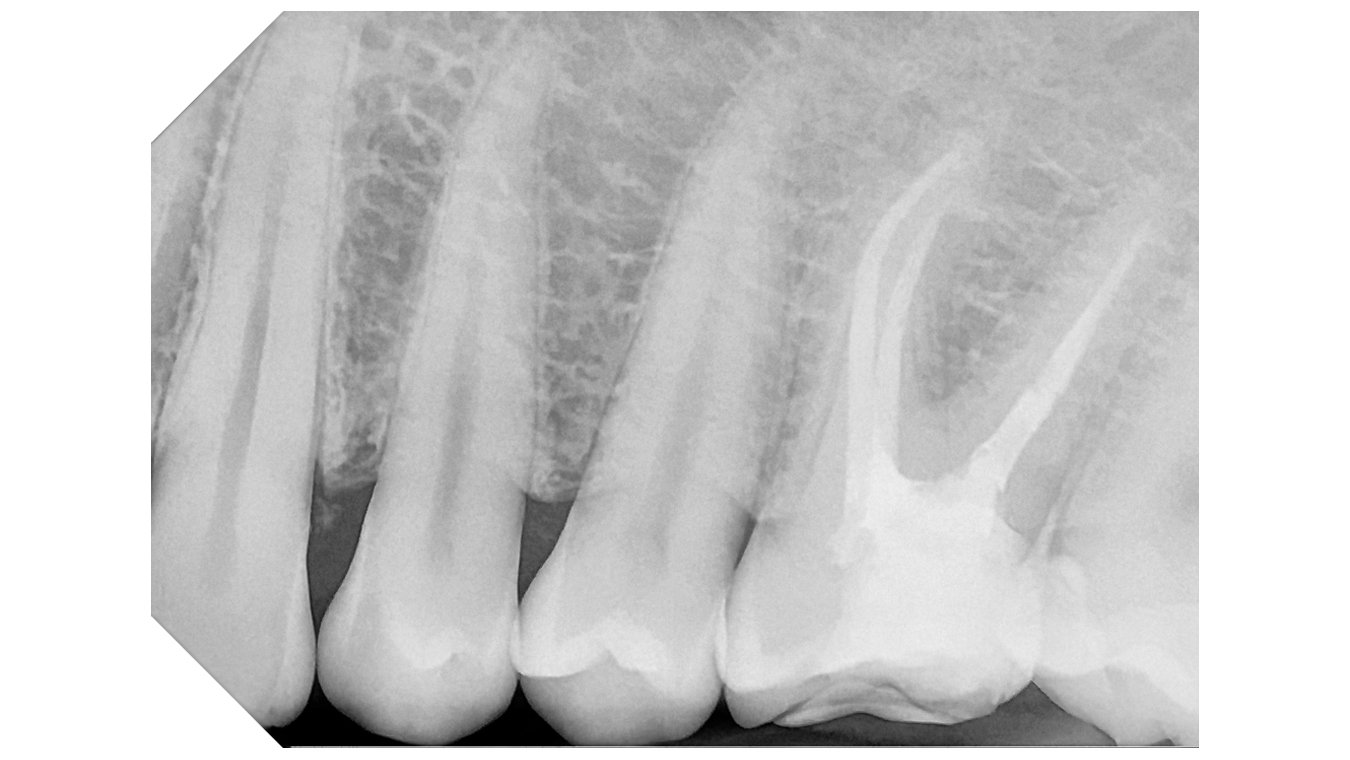

Integrated with the supplied software, the system offers advanced analysis tools and a selection of specific filters to improve image readability in line with clinical requirements:

Default:

High Contrast

High Details

Soft Tissue Preserving

Caries Revealing